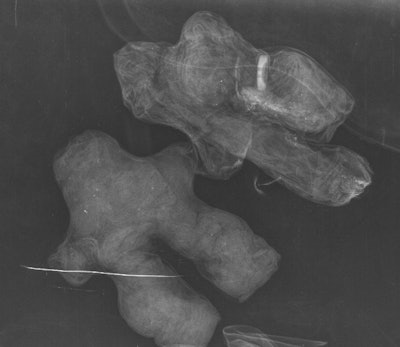

The researchers used a flat-panel digital radiography (DR) system (Clisis, Primax) to examine the objects: Five were individual dolls made of black or red fabric, while one was a pair of dolls bound together with a white cord -- one doll was made of black fabric and the other was made of white fabric. Both a radiologist and a medical anthropologist read the images taken of the dolls on film and on a workstation (JOFRI, December 2015, Vol. 3:4, pp. 221-225).

Two of the dolls made of black fabric included human hair on the head; one of these also included hair on the genital area, which led Charlier's group to characterize it as male. This doll was found to have a button inserted in its right leg, which was bent and shorter than the left leg.

"[The button] could be used to refine the identification of the target subject," Charlier and colleagues wrote.

Two of three red cloth dolls appeared to represent men of different sizes, with hair incorporated at the head and the genitals. One of these dolls had a staple in its filling. The third red doll appeared to have been made with features suggesting a woman's hips; the x-ray showed two separate zippers or fragments of the same side of a zipper.

"The presence of the zipper elements inside of the doll could constitute a love charm which joins and holds two things together," the authors wrote.